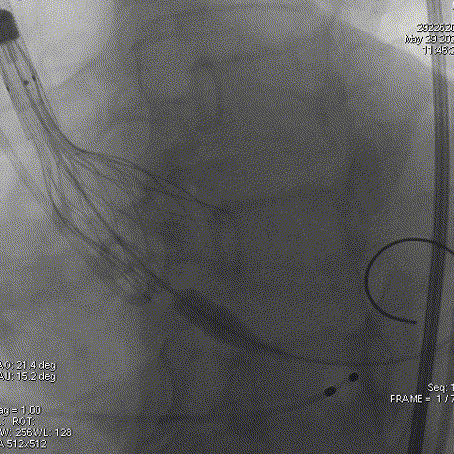

主动脉根部造影

导丝跨瓣

球囊预扩

输送器过弓

瓣膜定位

工作位造影